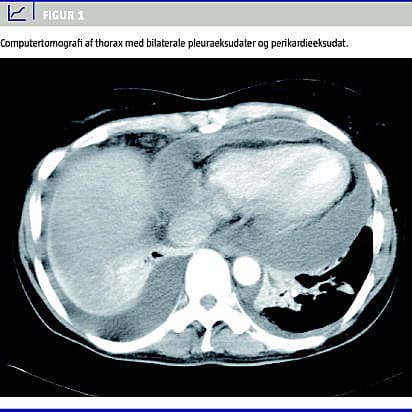

Ekkografi viste normal funktion af hjertet, men et perikardieeksudat på tre centimeter, der ikke var hæmodynamisk betydende. Computertomografi (CT) af thorax bekræftede fund af bilaterale pleuraeksudater samt perikardieeksudat. Der var ingen rumopfyldende processer eller tumorsuspekte forandringer (Figur 1 ).